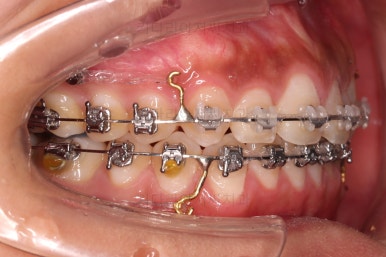

미니스크류를 식립을 하고요.

뒤로 뒤로 당겨줍니다.

만족하실 때까지 당겨줍니다.

교합도 신경 써주고요.